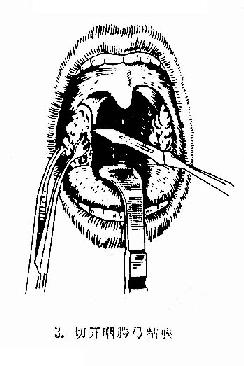

(2)剥离:用血管钳或剥离器插入舌腭弓切口,并向上后将扁桃体上极游离,然后用扁桃体钳夹持扁桃体上极,再以剥离器由上向下将扁桃体在其被膜外下周围组织分离,直至其下极。

图6-2 扁桃体切除术(剥离法)